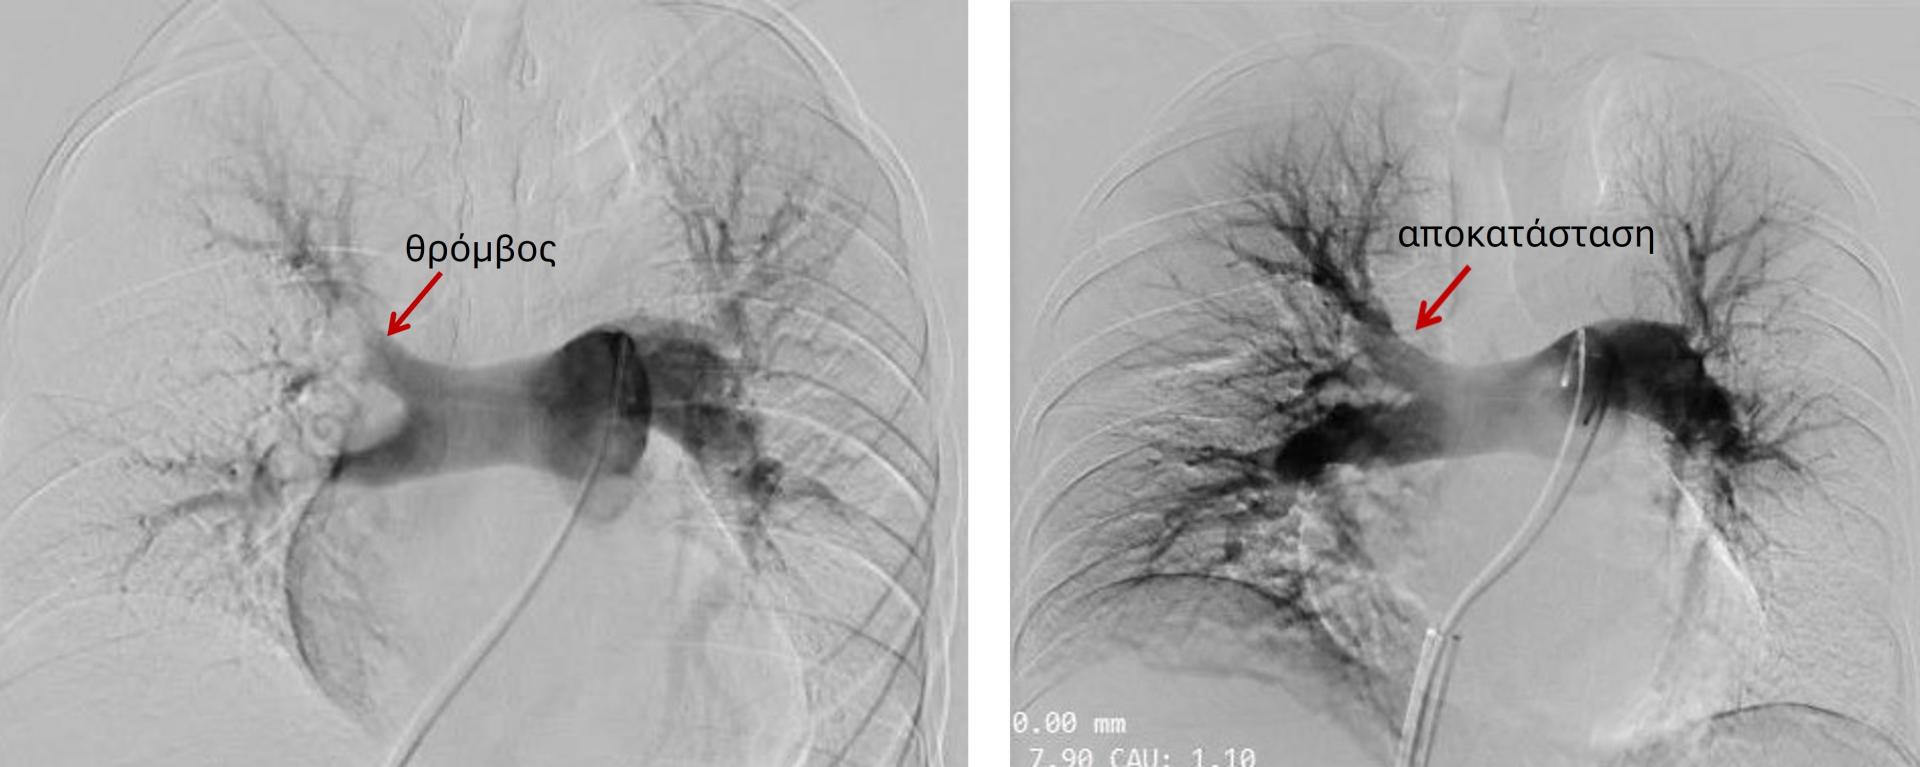

Η ασθενής προσήλθε στο Τμήμα Επειγόντων της Κλινικής με έντονη δυσκολία στην αναπνοή, χαμηλό οξυγόνο, οριακά χαμηλή πίεση και ταχυκαρδία λόγω της παρουσίας μεγάλης ποσότητας θρόμβου στις αρτηρίες που δίνουν αίμα στους πνεύμονες (πνευμονική εμβολή). Το δεξιό μέρος της καρδιάς φαινόταν να δυσκολεύεται ιδιαίτερα να στείλει αίμα στους πνεύμονες, με αποτέλεσμα να κινδυνεύει η ζωή της ασθενούς. Αφού έγινε άμεσα η σωστή διάγνωση, άρχισε η αντιπηκτική θεραπεία και η ασθενής εισήχθη στη Μονάδα Εντατικής Θεραπείας. Τα αποτελέσματα των αιματολογικών εξετάσεων, ο υπέρηχος καρδιάς και η αξονική τομογραφία, επιβεβαίωσαν την κρισιμότητα της κατάστασης. Με πρωτοβουλία του κ. Καπετανόπουλου και σε συνεργασία με την εταιρεία Risalko, συστήθηκε και οργανώθηκε άμεσα η απόπειρα αφαίρεσης του θρόμβου με τη συσκευή FlowTriever μέσω καθετήρα από τη φλέβα του ποδιού με τοπική αναισθησία. Η επέμβαση οδήγησε σε αφαίρεση μεγάλης ποσότητας θρόμβου και άμεση ανακούφιση της ασθενούς. Η έκβαση ήταν άριστη με την ασθενή να εξέρχεται της εντατικής το επόμενο κιόλας πρωί, ενώ μετά από 3 ημέρες νοσηλείας στο θάλαμο πήρε εξιτήριο για το σπίτι με την κατάλληλη αγωγή και χωρίς να χρειάζεται οξυγόνο.